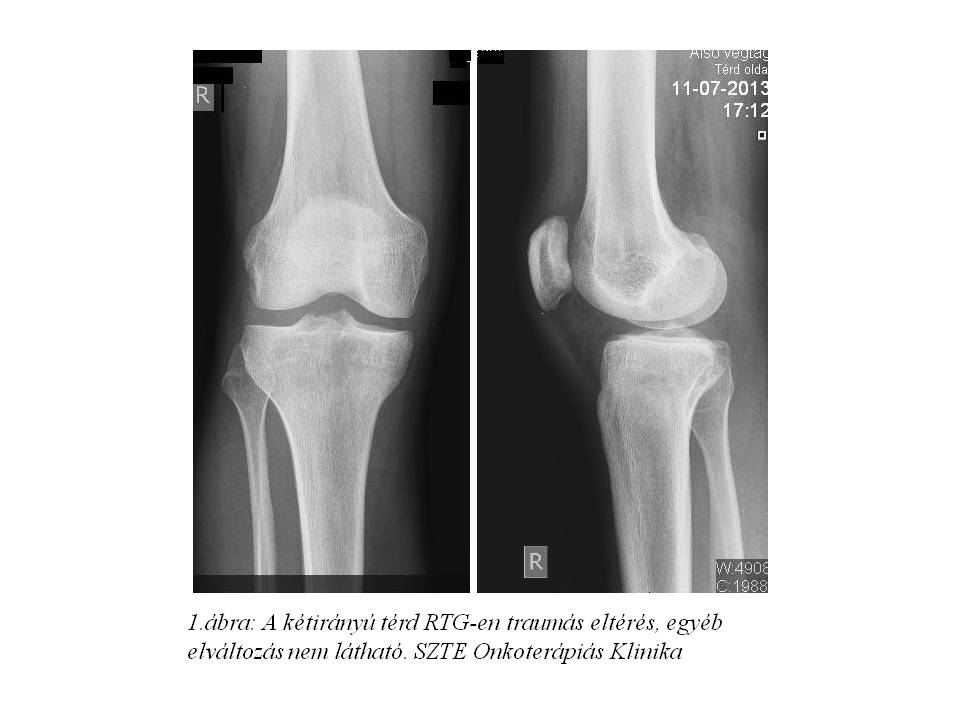

dolt. Júliusra a fájdalom fokozatosan erősödött, RTG vizsgálat (1. ábra) készült, mely traumás eltérést nem írt le, lokális Diprophos-Diclac terápia indult. Fájdalma nem mérséklődött, ellenben folyamatos dagadás és térdhajlati terime növekedést észlelt, MRI (2. ábra, 3. ábra) készült, mely alapján sürgős biopsia történt. A tibia biopsia szövettana desmoplastikus kis kereksejtes tumort (DSRCT) véleményezett, habár a tumor lokalizációja extrém ritka. A DSRCT agresszív, malignus tumor, kifejezetten rossz prognózissal (median túlélés: 17-25 hónap). Általában a primer tumor a hasüregben alakul ki, peritonealis terjedés az elsődleges, majd limfatikus és hematogén áttétképződés, különösen a májba. Staging vizsgálatai során disszeminált csontérintettséget, limfatikus és pulmonalis metasztázisokat írtak le (4. ábra, 5. ábra). A szakirodalom áttekintését követően 2013.10.14-én VIDE (Vincristine, Ifosfamide, Doxorubicin, Etoposide) kemoterápiás, ill. a disszeminált csontérintettség miatt zoledronsav kezelést kezdtünk. A felvételkor csak segédeszközzel, és igen nehezen mozgott, idejének több mint 50%-át ágyban töltötte, állandó medencefenék, keresztcsonti zsibbadásról, vizelet- és széklet-ürítési panaszokat említett.